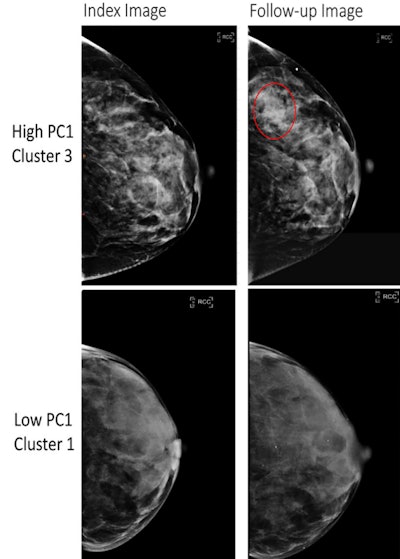

Full-field digital mammography (FFDM) images in a 52-year-old woman show a high-risk phenotype (top), and FFDM images in a 58-year-old woman show a low-risk phenotype (bottom). The high-risk phenotype was defined by having high values of the first principal component (PC1) and was assigned to cluster 3 (top row), and the low-risk phenotype was defined by having low values of the PC1 and was assigned to cluster 1 (bottom row). The index images (left side; before any diagnosis of cancer) are provided as well as follow-up images obtained at either the time of cancer diagnosis (for the high-risk phenotype, top right) or at the last follow-up (low-risk phenotype, bottom right). The red circle indicates the location of subsequent breast cancer. Both women had a BI-RADS breast density of C. The woman at high risk for breast cancer was Black and the woman at low risk for breast cancer was white.RSNA

The principal components also showed similar associations among Black and white women (p = 0.23). And they were also positively associated with false-negative findings (p = 0.004) and symptomatic interval cancers (p = 0.006).